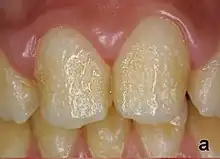

Pitting enamel hypoplasia

Enamel hypoplasia can take a variety of forms, but all types are associated with a reduction of enamel formation due to disruption in ameloblast production.[1] One of the most common types, pitting enamel hypoplasia (PEH), ranges from small circular pinpricks to larger irregular depressions.[2] Pits also vary in how they occur on a tooth surface, some forming rows and others more randomly scattered.[3] PEH can be associated with other types of hypoplasia, but it is often the only defect observed.[4] Causes of PEH can range from genetic conditions to environmental factors, and the frequency of occurrence varies substantially between populations and species, likely due to environmental, genetic and health differences. The most striking example of this is in Paranthropus robustus, with half of all primary molars, and a quarter of permanent molars, displaying PEH defects, thought to be caused by a specific genetic condition, amelogenesis imperfecta.[1]

Each pit is linked to the ceasing of ameloblasts at a particular point in enamel formation. Sometimes, only a couple of ameloblasts stop forming enamel, leading to small PEH defects, with large pits forming when hundreds of these enamel-forming cells stop production.[6] This does not occur in other forms of enamel hypoplasia, such as linear and plane-form, in which all ameloblast activity is affected.[4] Typically with PEH described in archaeological reports, researchers can not specify a cause, with a non-specific stress often concluded. However, in modern clinical studies it is often possible to suggest a cause and these can include the following conditions:[1]